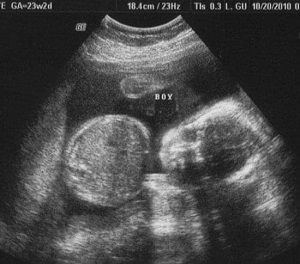

- Median weight for dichorionic twins: 1lbs, 5oz

- Median weight for monochorionic twins: 1lbs, 4oz

Ultrasound Photos at 23 Weeks Pregnant With Twins